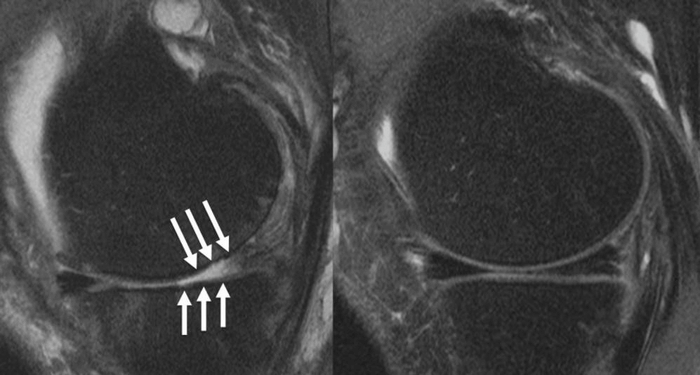

All patients underwent MRI scans two years prior to injection, at the time of injection, and after injection. The team assessed their scans using whole-organ magnetic resonance imaging score (WORMS) to detect the severity of their osteoarthritis — examining the meniscus, bone marrow lesions, cartilage, joint effusion, and ligaments.

They were then able to compare differences in scores between the initial and follow-up scans. Results show that steroid injections significantly influenced arthritis progression, particularly in the lateral meniscus, lateral cartilage, and medial cartilage.

(CREDIT: RSNA and Upasana Upadhyay Bharadwaj, M.D.)